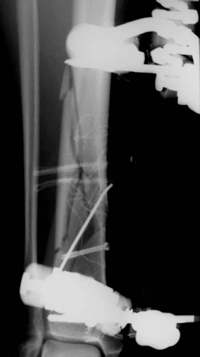

Distale Tibiafraktur mit Weichteilschaden

Die Fraktur reicht bis in das Sprunggelenk

Die Stabilisierung erfolgte minimal invasiv.

2Tage nach der Operation. Schrauben und Drähte wurden weichteilschonend mit Stichincisionen eingebracht.